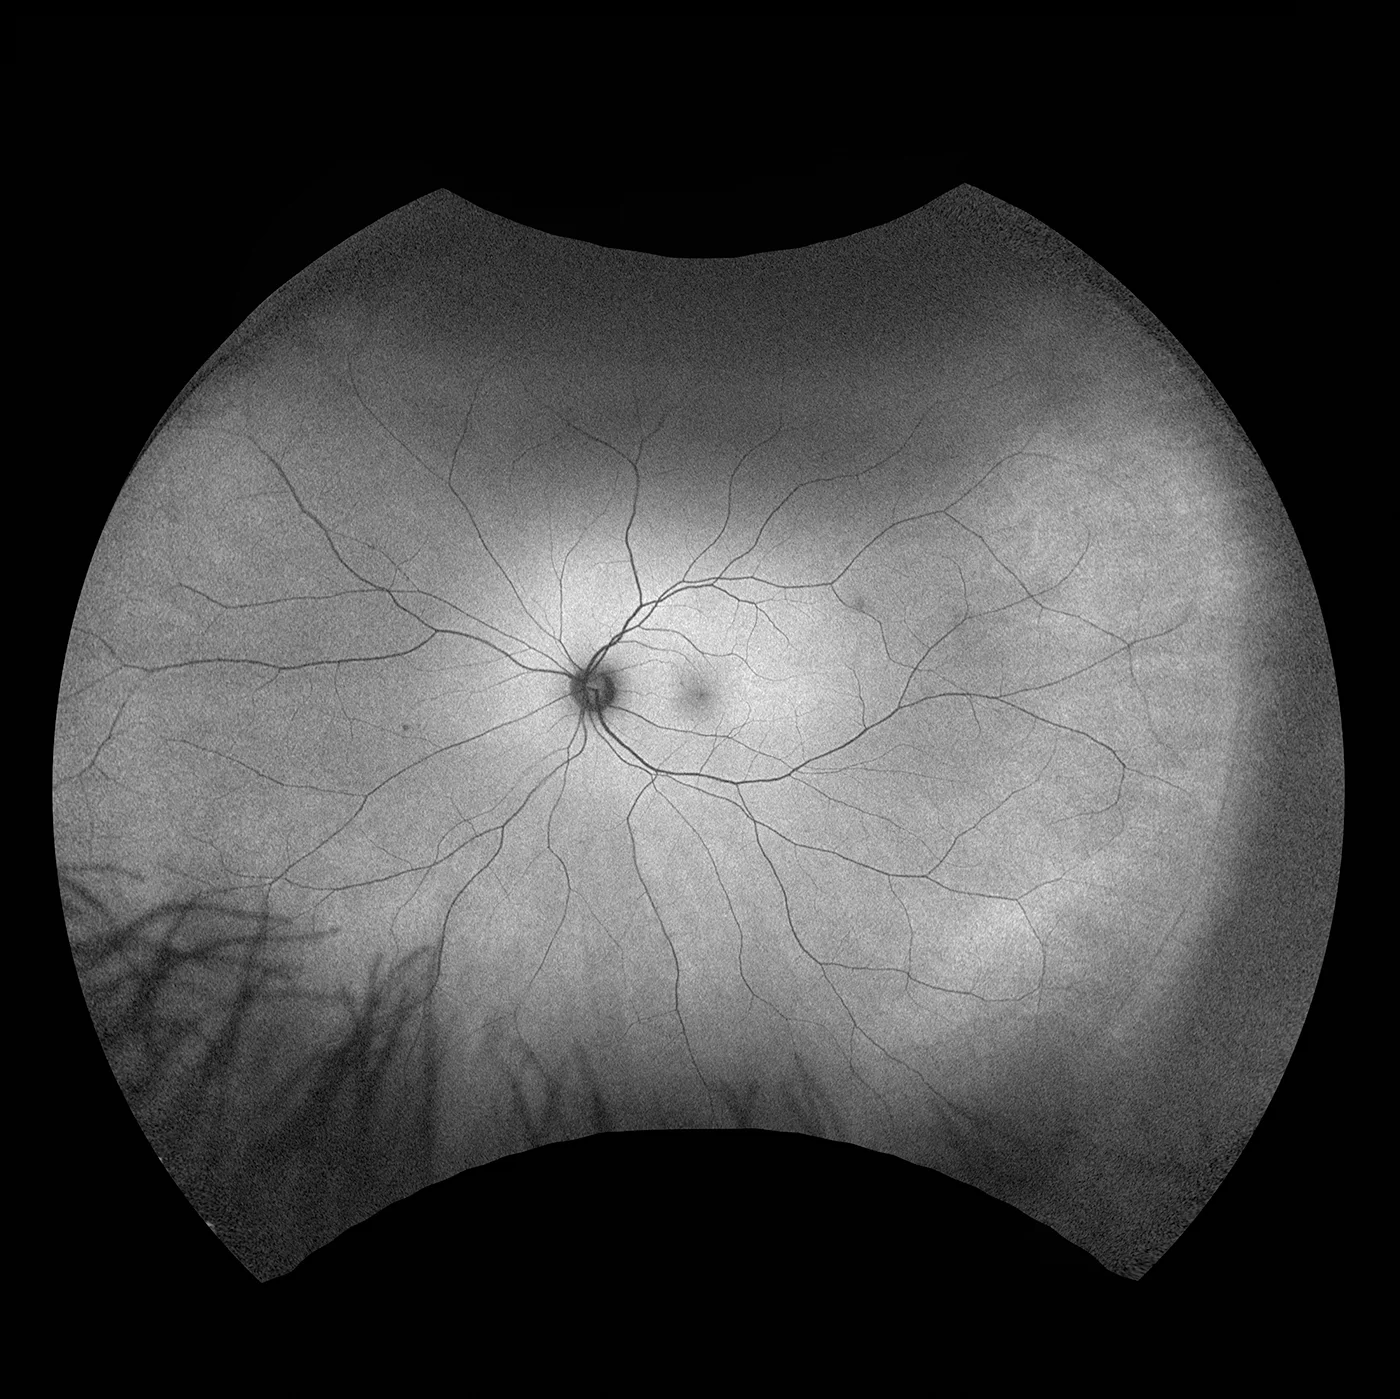

MonacoPro bietet Ihnen faszinierende neue Möglichkeiten, Ihre klinischen Untersuchungen zu vervollkommnen. Als einzige Ultra-Weitwinkel- Bildgebung der Netzhaut mit integriertem SD-OCT liefert Ihnen MonacoPro ein 200° optomap-Bild in weniger als ½ Sekunde und erstellt zudem 40°-OCT-Querschnittsaufnahmen von Netzhautstrukturen. MonacoPro ermöglicht eine schnelle multimodale Bilderfassung mit Farb-, Autofluoreszenz- und OCT-Scans für beide Augen in nur zwei Minuten.

optomap farbe rg und optomap plus (Rot und Grün Laser): |

optomap plus: 14 μm |